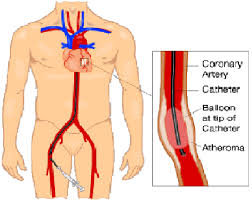

Overview

Package includes:

Days in hospital : 3 to 4 Days (For patient and one attendant)

Days in hotel : 7 Days (For patient and one attendant)

Room type in hospital : Shared

Room type in hotel : Private

Hotel category: Standard

Value added benefits of the Coronary Angioplasty:

Ø Doctor consultation charges

Ø Lab tests and diagnostic charges

Ø Room charges inside hospital during the procedure

Ø Surgeon Fee

Ø Nursing charges

Ø Hospital surgery suite charges

Ø Anesthesia charges

Ø Routine medicines and routine consumables (bandages, dressings etc.)

Ø Food and Beverages inside hospital stay for patient and one attendant.

Extra benefits:

ü Interpreter

ü Visa assistance

Ø Site tourism of the city

Ø Follow up with the doctor

Ø Airport pick up and drop

Ø Free online consultation with the doctor

Ø Priority appointments with the doctor

Ø Room upgrade from sharing to private